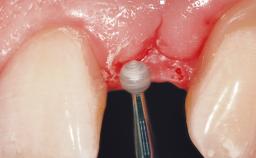

Late Flapless Placement of an Implant in a Maxillary Left Central Incisor Site

Soft Tissue Grafting Simultaneous

Bone Volume Deficient horizontally, requiring prior grafting